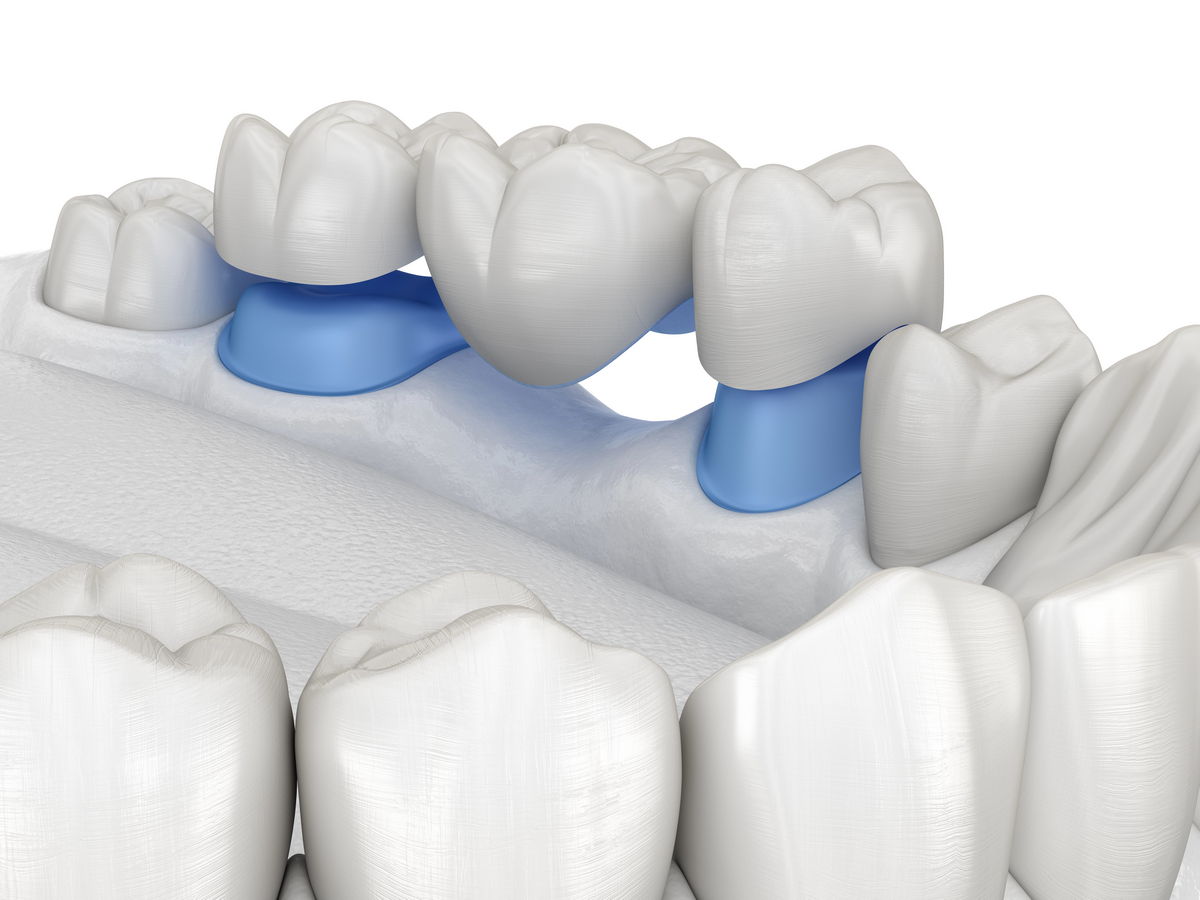

Teleskopbrücke

Wenn genügend eigene Zähne vorhanden sind, können wir eine Teleskopbrücke anfertigen, die nicht in den Gaumen hineinragt. Wenn nur wenige eigene Zähne vorhanden sind, empfehlen wir eine Teleskopprothese, die im Gaumen einen kleinen Bügel aufweist, der beide Seiten der Prothese miteinander verbindet.

Eine Teleskopprothese ist eine „Teilprothese, die an Teleskopkronen befestigt ist“. Teleskopkronen haben zudem eine Stütz- und Haltefunktion. Es handelt sich um eine herausnehmbare Zahnprothese, die zum Ersatz fehlender Zähne dient.

Teleskopkronen sind Doppelkronen. Sie bestehen aus zwei übereinanderliegenden Kronen. Die inneren Kronen (Primärteleskope) sind fest zementiert, die äußeren Kronen (Sekundärteleskope) sind an der herausnehmbaren Teilprothese befestigt. Die Teleskopprothese wird durch statische Reibung zwischen Primär- und Sekundärkrone an Ort und Stelle gehalten..